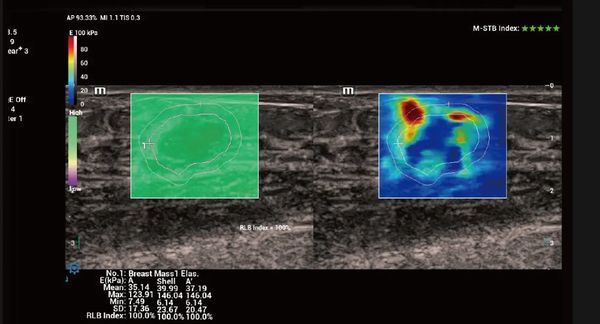

Similar al espíritu inherentemente rápido y nítido de un jaguar, Vetus 9 ofrece imágenes 10 veces más rápidas, enfoque dinámico de píxeles y tecnologías originales de recuperación de señal ecográfica, lo que permite a los veterinarios enfrentarse a todos los escenarios clínicos con facilidad.

La plataforma ZST+ es una innovación extraordinaria, que representa una evolución de la tecnología de ultrasonidos. Transforma las métricas de los ultrasonidos de la formación de haces convencional al procesamiento basado en canales. Supera la tradicional limitación de compensación entre resolución espacial, resolución temporal y uniformidad tisular, proporcionando una calidad de imagen excepcional en diversos escenarios clínicos veterinarios y ofreciendo una confianza notable.